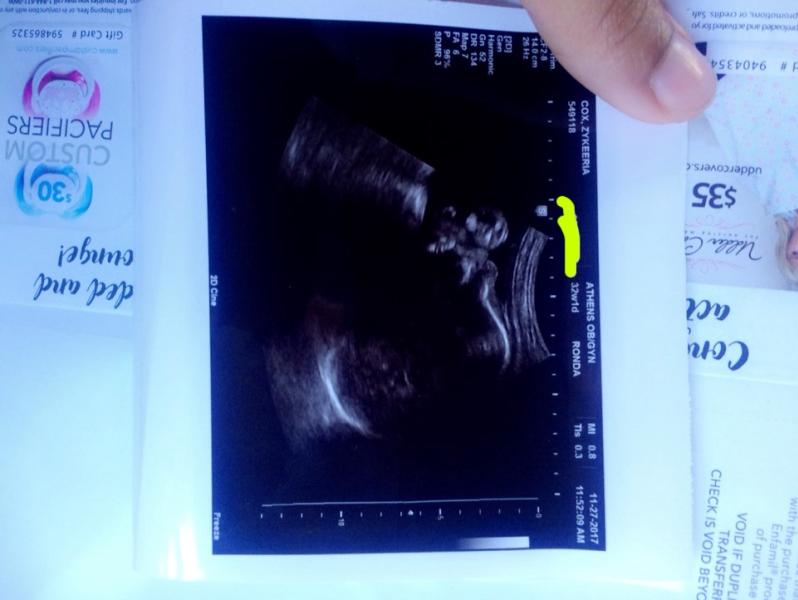

I’m soooo ready to meet my son!!!! He has a huge head like his dad & sisters😭😭😭😭😭😂❤️❤️ Khaza Kenyae Malik Washington